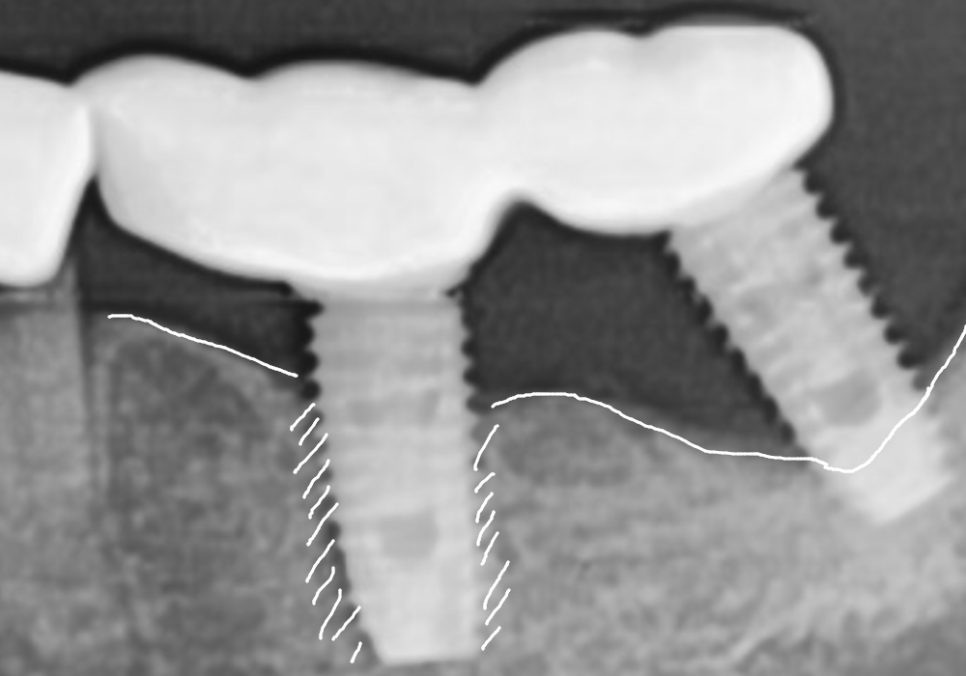

방사선 사진을 보니 상태가

더 명확했는데요.

바로 옆 임플란트(#36)는

뼈가 꽉 차 있는 반면,

맨 끝 임플란트(#37)는

뿌리 주변의 뼈가 까맣게 녹아내려

텅 비어 있는 상태였습니다.

보통 이 정도로 뼈가 녹으면

임플란트가 심하게 흔들려야 정상이에요.

하지만 이 환자분은 앞뒤 임플란트 보철물을

하나로 묶어놓았기에,

망가진 임플란트가 앞쪽 임플란트에

고정되어 있어 흔들림을 전혀 못 느끼셨던 것이죠.

통증도 없고 흔들리지도 않으니

뼈가 다 녹을 때까지 모르고 계셨던 거예요.ㅜㅜ